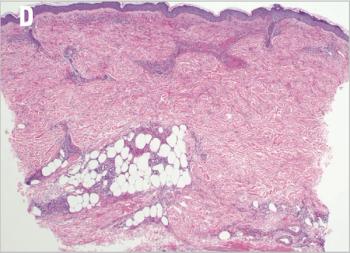

In this installement of Clinical Quandaries, Abigail Mateos-Soria, MD, and colleagues present a case of an 38-year-old woman who has a 3-month history of fatigue, dyspnea, significant weight loss, and severe left flank pain.